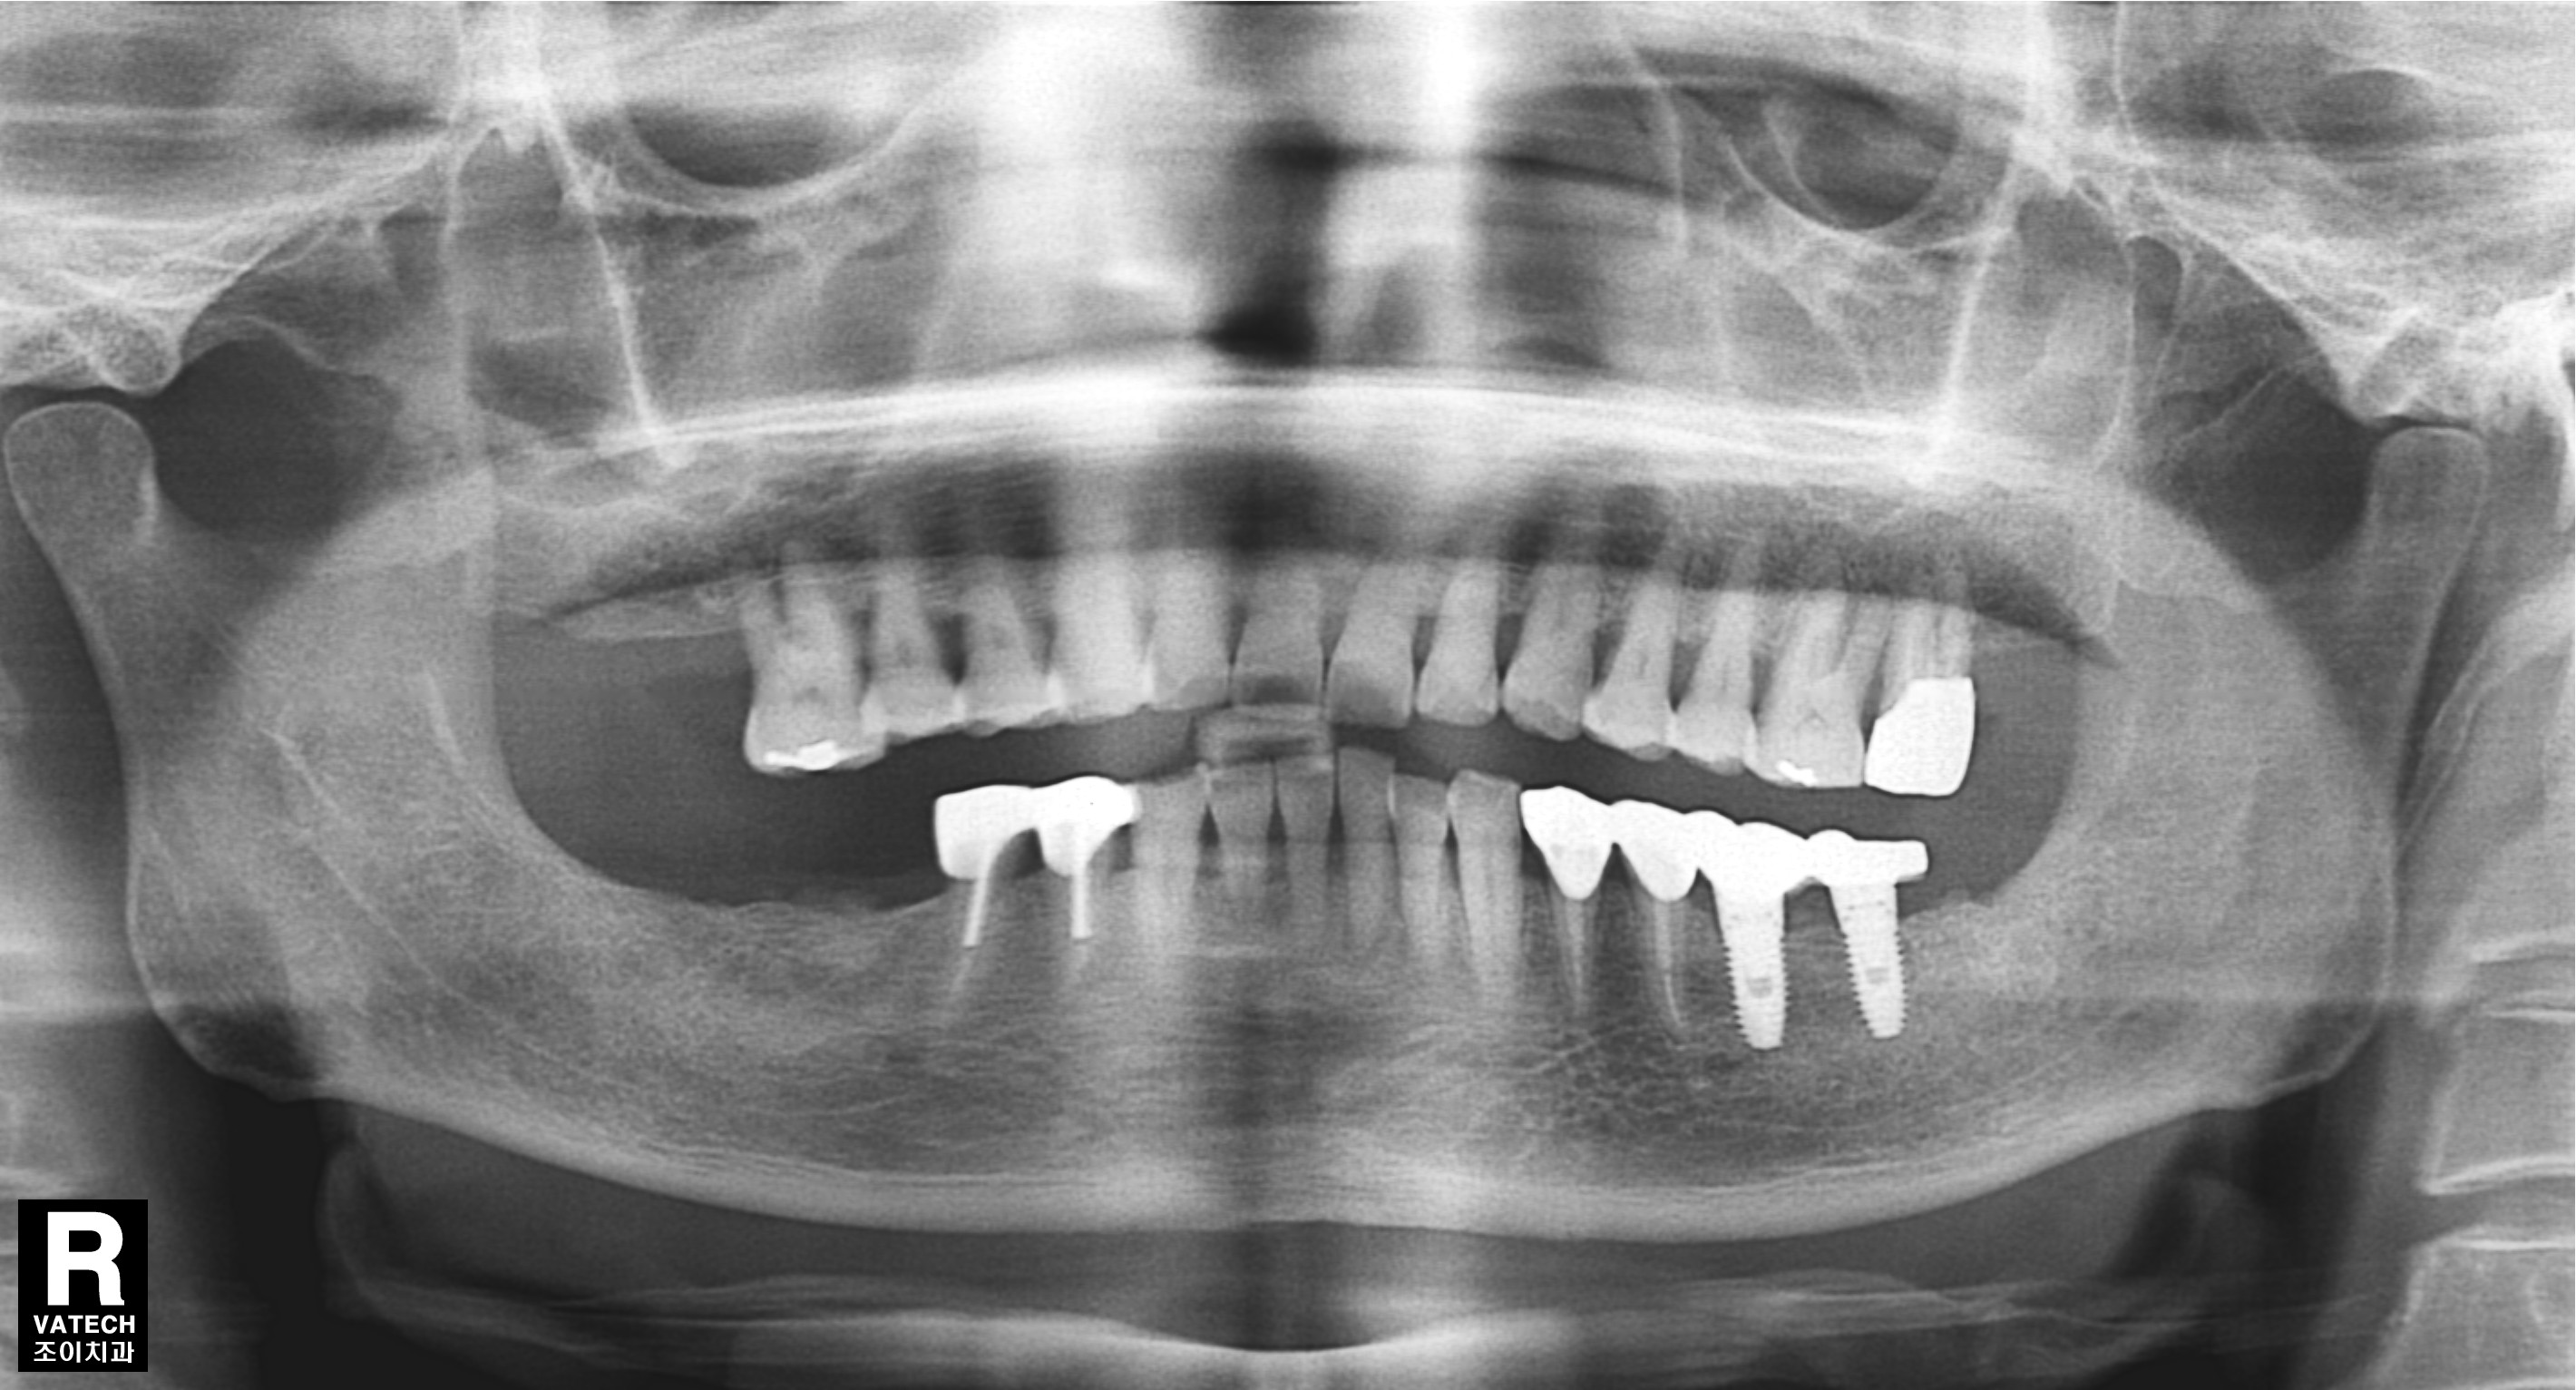

[임플란트] 제목 : 오래된 보철의 수리 및 임플란트

후방연장된 보철은 그 안에서 2차우식이 일어나기 쉽습니다.

문제가 된 보철을 제거하고 재치료한 례입니다.